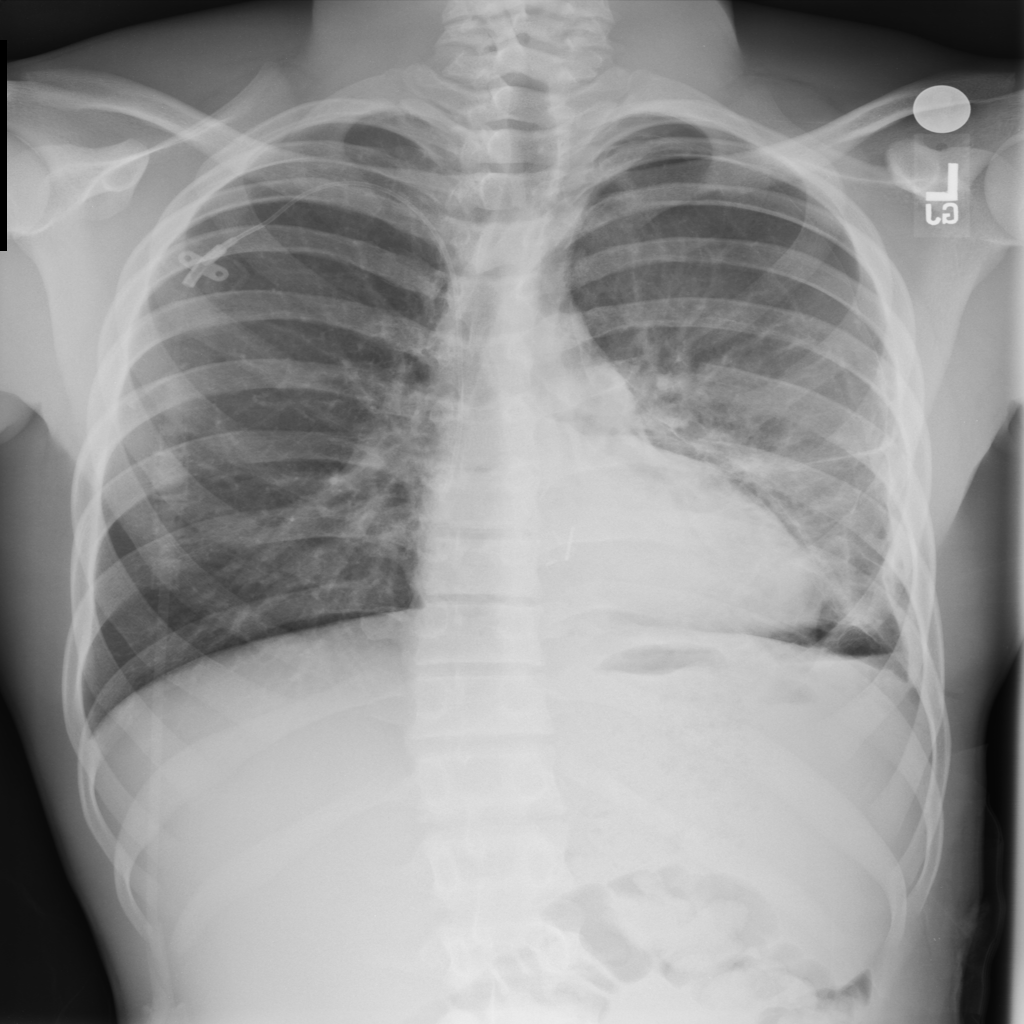

Showing up to 90 reference images for Pneumothorax.

PAT-4639 · IMG-020Pneumothorax

PAT-4639 · IMG-020

PA